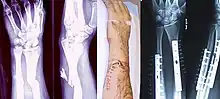

![]() | |

| Internal and external views of an arm with a compound fracture, both before and after surgery | |